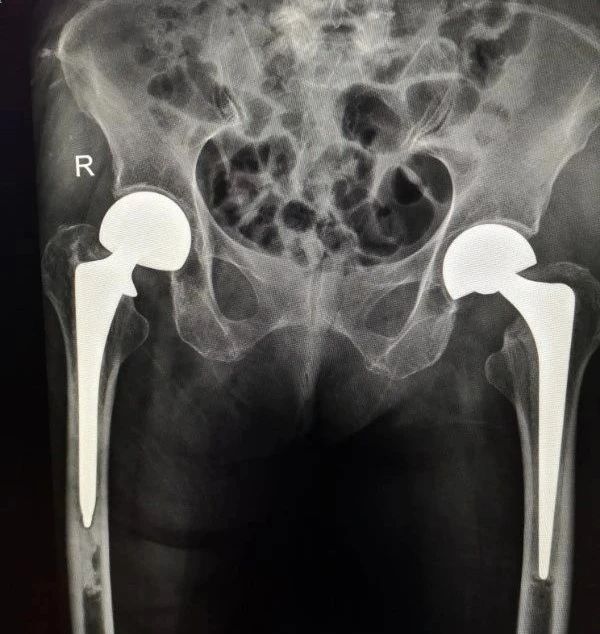

曾經(jīng)的辣妹子歷經(jīng)生活的磨難終于熬成了婆。 然而,上蒼并沒(méi)有因?yàn)樗纳屏记趧诙拼?mpchecktext contenteditable="false" id="1623199119977_0.1877011081056119"> 在黃娭毑60多歲時(shí)做了乳腺全切手術(shù)、70多歲把膽囊切除了、85歲時(shí)右側(cè)股骨頸骨折,做了人工髖關(guān)節(jié)置換……這些手術(shù)都在岳陽(yáng)愛(ài)康醫(yī)院做的。 這不,不久前黃娭毑在家又摔一跤,左股骨頸骨折,需要做左側(cè)人工髖關(guān)節(jié)置換術(shù),再次住進(jìn)了岳陽(yáng)愛(ài)康醫(yī)院。

骨科李強(qiáng)主任馬上請(qǐng)全院專家會(huì)診,帶領(lǐng)科室制定詳細(xì)的手術(shù)方案。 在5.20這個(gè)特別有愛(ài)的日子里成功為黃娭毑進(jìn)行了左側(cè)人工半髖關(guān)節(jié)置換術(shù)。